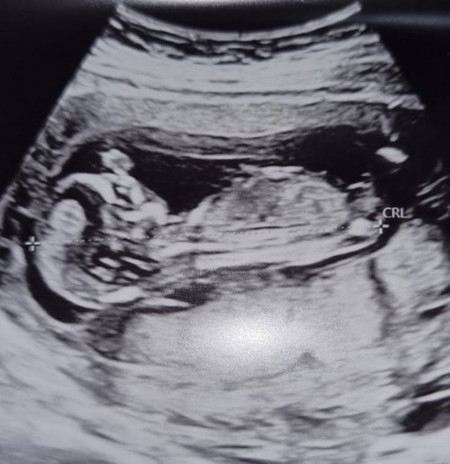

ลูกสาว หรือ ลูกชาย คะ ใครดูเป็นบ้าง

14w แล้ว แต่หมอยังไม่แจ้งเพศค้า ไม่รู้ว่าดูได้หรือยัง รูปซาวล่าสุดคะ

รูปนี้ไม่สามารถระบุเพศได้ค่ะเป็นส่วนลำตัวของน้อง ต้องเป็นรูปหว่างขาถึงจะบอกได้ค่ะแม่